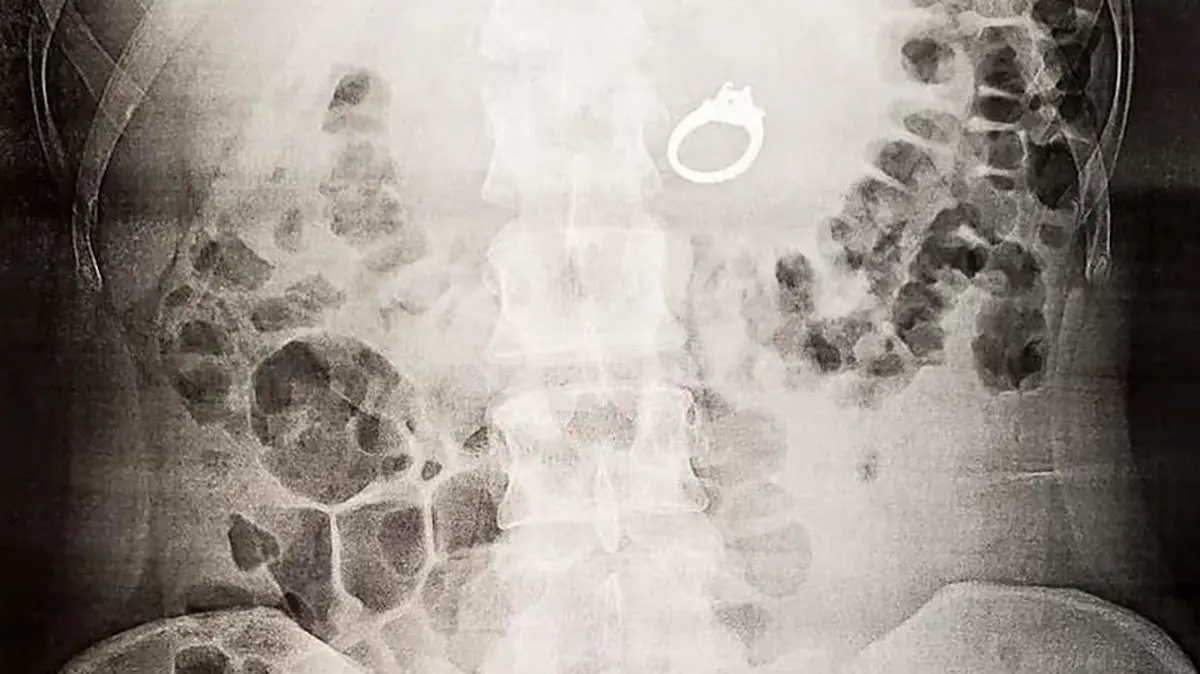

بلعیدن حلقه نامزدی توسط یک زن در خواب/ پزشکان امریکایی شوکه شدند + عکس ها

حوادث رکنا: کابوس و رویاهای وحشتناک زن جوان را وادار به بلعیدن حلقه نامزدی اش کرد.

از قرار معلوم، زن جوان هنگام دیدن خواب های وحشتناک حلقه نامزدی اش را بلعید و زمانی که از خواب بیدار شد متوجه ناپدید شدن حلقه اش نیز شد.

زن جوان در این باره گفت: خواب بودم و رویاهای بدی می دیدم در خواب متوجه شدم که حلقه ام را بلعیدم اما تصور می کردم که همه چیز خواب است و این اتفاق در دنیای خواب افتاده اما هنگام بیداری وقتی حلقه ام را پیدا نکردم برای اطمینان از این موضوع خود را به بیمارستان رساندم و پزشکان نیز با انجام سی تی اسکن این موضوع را تائید کردند آنها شوکه شده بودند و خوشبختانه توانستند با عمل جراحی آن را از شکمم خارج کنند.